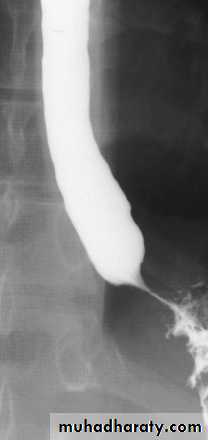

Stricture

Benign vs. malignant Causes Specific locationContrast study EUS CT